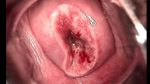

婦科leep錐切手術(shù) CIN2-3

• CIN 2-3 leep術(shù)后CIN 2-3 leep術(shù)后